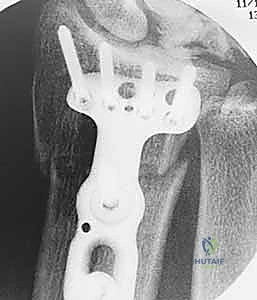

- الأشعة السينية (X-Rays): وهي الخطوة الأولى. تساعد الأشعة السينية في رؤية التغيرات في كثافة العظم الهلالي (المرحلة الثانية)، أو رصد أي انهيار في العظم (المرحلة الثالثة)، وكذلك تقييم طول عظمي الكعبرة والزند لاكتشاف وجود "تباين زندي سلبي".

- التصوير المقطعي المحوسب (CT Scan): يُستخدم أحياناً للحصول على صور ثلاثية الأبعاد وعالية الدقة للعظم الهلالي لتقييم مدى الانهيار والتفتت بدقة بالغة، مما يساعد الدكتور هطيف في التخطيط الجراحي الدقيق قبل العملية.

| تقصير عظم الكعبرة (Radial Shortening) | تقصير الكعبرة بمقدار 2-3 ملم لتخفيف الضغط عن العظم الهلالي وتوزيع الأحمال. | المراحل II و IIIA مع وجود تباين زندي سلبي. | ممتازة جداً، تخفف الألم وتوقف تطور المرض بشكل فعال. |